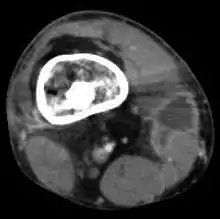

Radiographs and CT are the initial method of diagnosis, but are not sensitive and only moderately specific for the diagnosis. They can show the cortical destruction of advanced osteomyelitis, but can miss nascent or indolent diagnoses.[22]

Confirmation is most often by MRI. The presence of edema, diagnosed as increased signal on T2 sequences, is sensitive, but not specific, as edema can occur in reaction to adjacent cellulitis. Confirmation of bony marrow and cortical destruction by viewing the T1 sequences significantly increases specificity. The administration of intravenous gadolinium-based contrast enhances specificity further. In certain situations, such as severe Charcot arthropathy, diagnosis with MRI is still difficult.[22] Similarly, it is limited in distinguishing avascular necrosis from osteomyelitis in sickle cell anemia.[23]

Nuclear medicine scans can be a helpful adjunct to MRI in patients who have metallic hardware that limits or prevents effective magnetic resonance. Generally a triple phase technetium 99 based scan will show increased uptake on all three phases. Gallium scans are 100% sensitive for osteomyelitis but not specific, and may be helpful in patients with metallic prostheses. Combined WBC imaging with marrow studies has 90% accuracy in diagnosing osteomyelitis.[24]

Diagnosis of osteomyelitis is often based on radiologic results showing a lytic center with a ring of sclerosis.[13] Culture of material taken from a bone biopsy is needed to identify the specific pathogen;[25] alternative sampling methods such as needle puncture or surface swabs are easier to perform, but cannot be trusted to produce reliable results.[26][27]